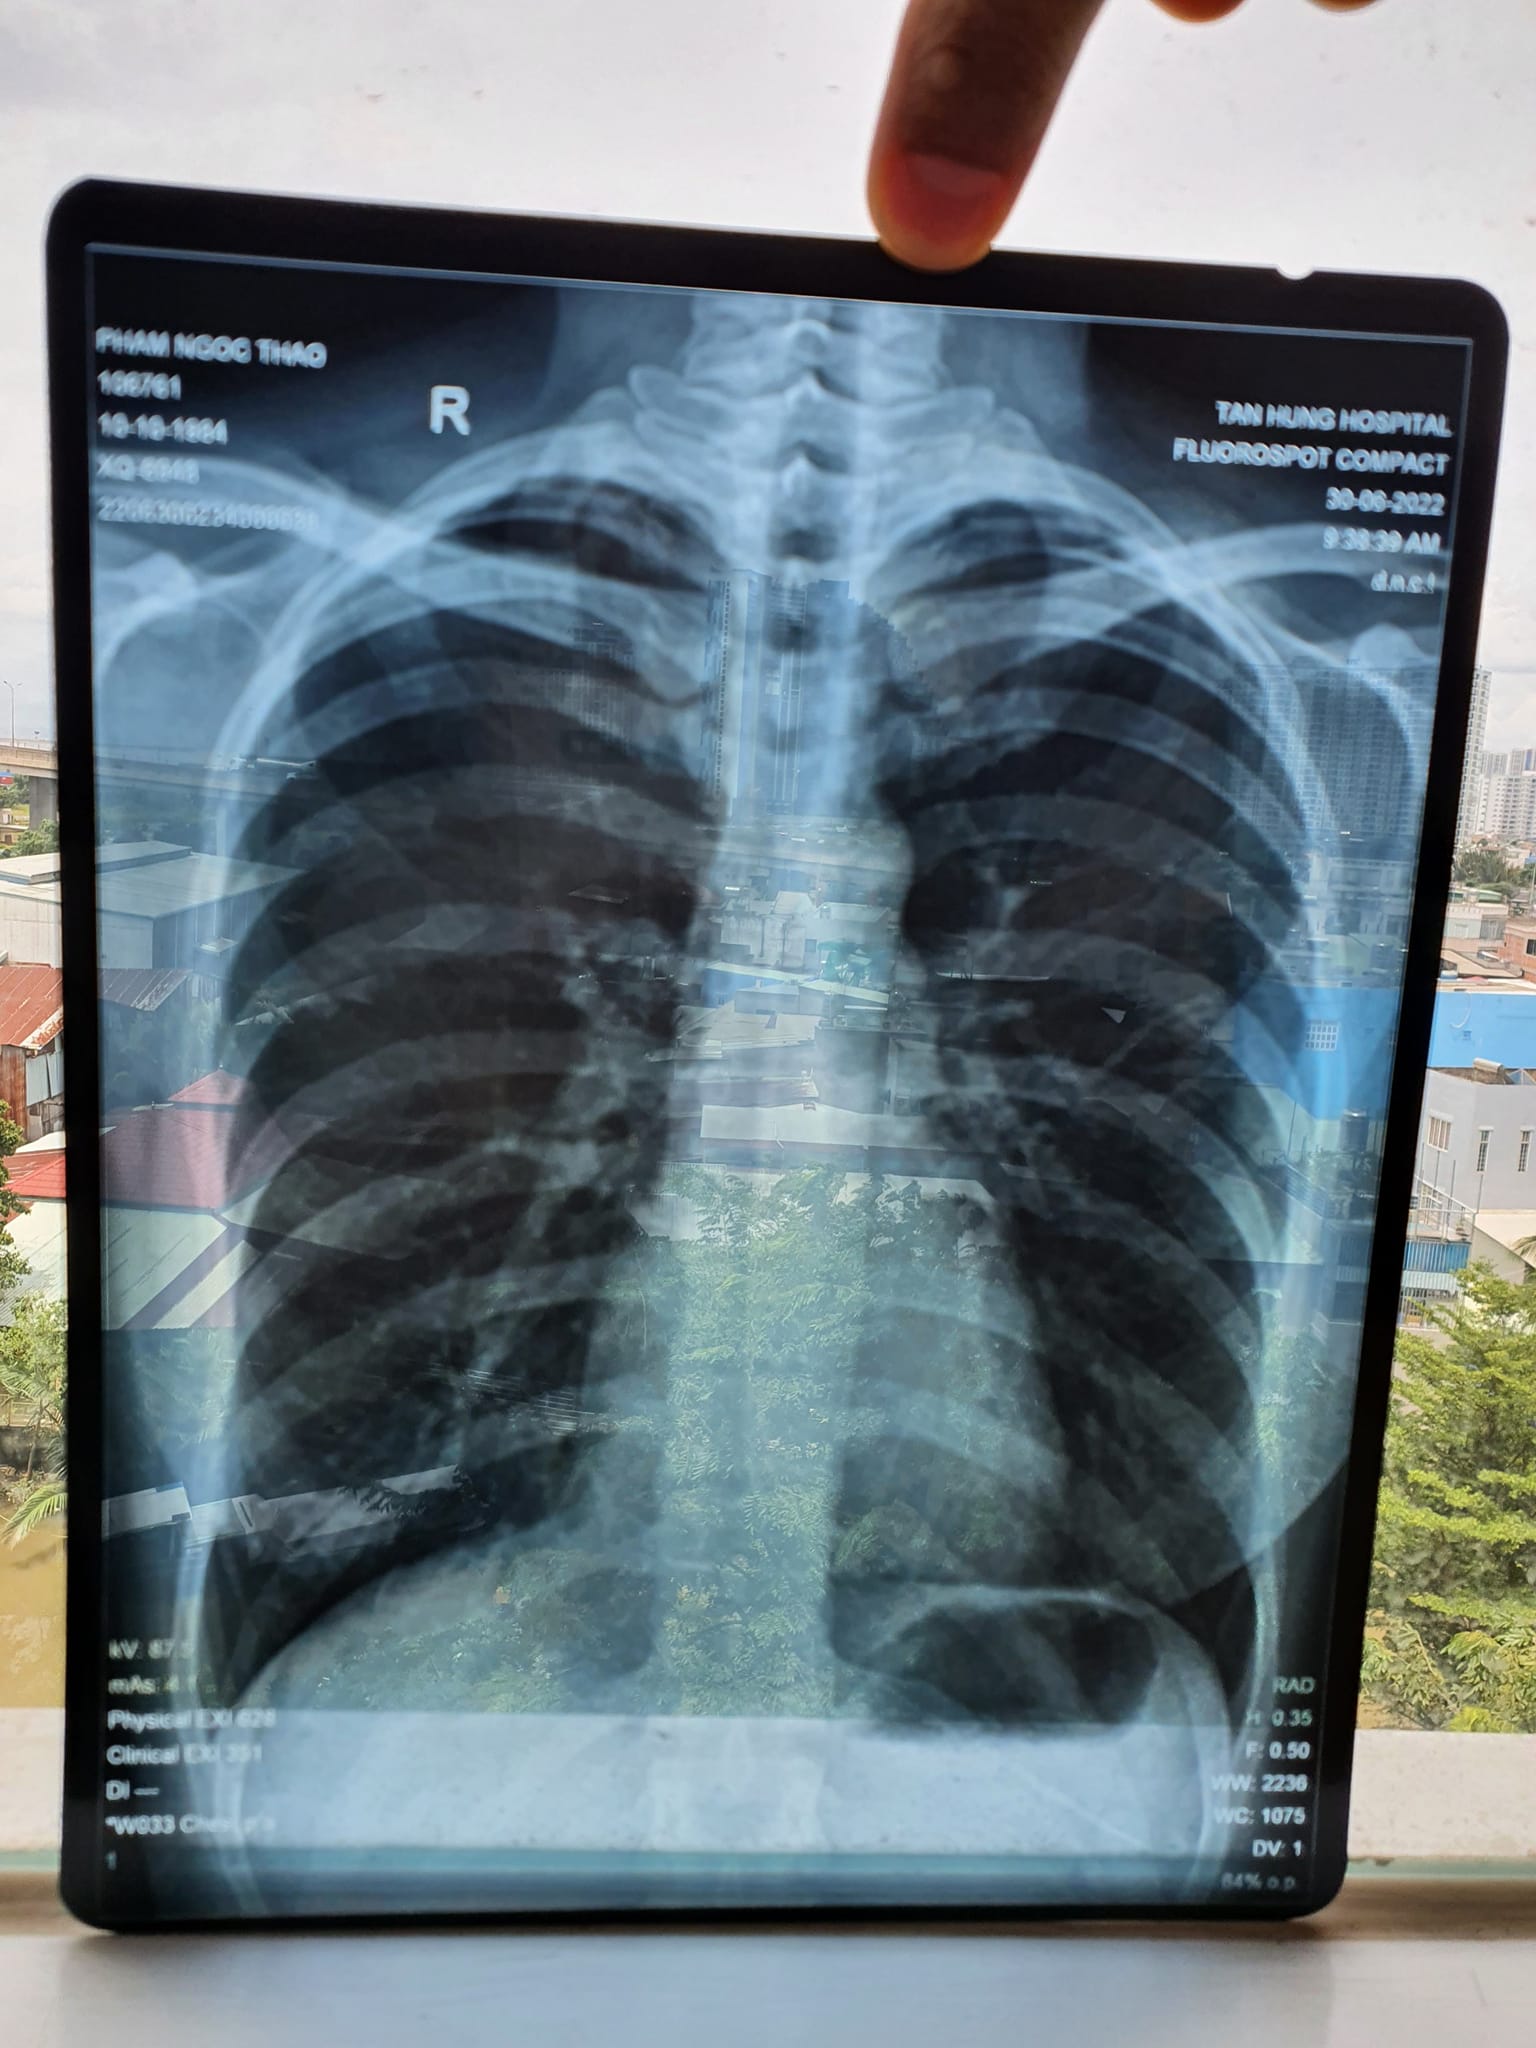

Kết quả X quang và CT sau khi chăm sóc sức khỏe bằng Năng lượng sinh học vào ngày 30/6/2022